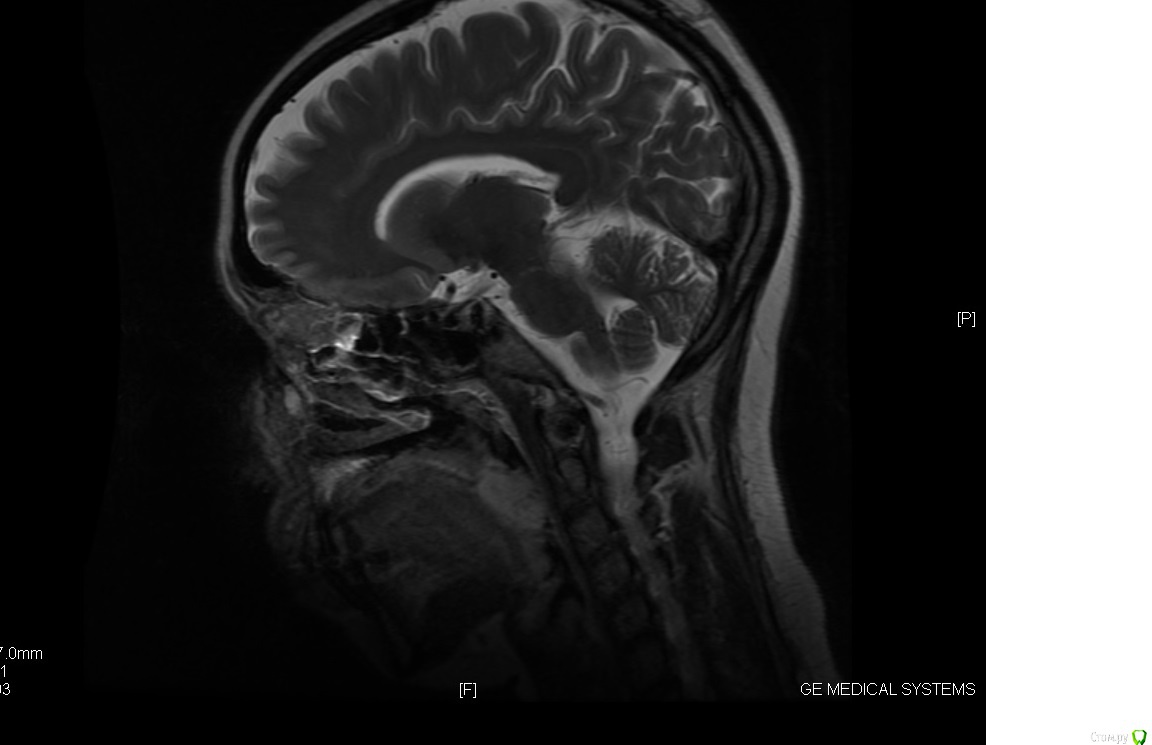

Chudo Опубликовано 14 октября, 2017 Поделиться Опубликовано 14 октября, 2017 Здравствуйте. Нужна консультация. Мне 30 лет, у меня остеопороз. 3 года после родов хожу лечить зубы как на работу (после родов состояние зубов плачевное, на панорамном снимке все видно). Сначала просто лечили кариес, удаляли нервы, ставили пломбы. У меня было две нижних 8 которые сильно сдавили мне все зубы. Мой врач все время говорила что надо ставить брекеты из-за неправильного прикуса, но денег и времени не было (маленький ребенок, отец инвалид 1 группы и муж в бесконечных командировках). В конце 2015 года я пошла удалять восьмерку, так как боль от давления на зубы стала нестерпимая. Располосовали щеку что бы поддеть 8 которая стояла горизонтально(снимок перед удалением 8 прилагаю). Зуб удаляли в Краевом клиническом стоматологическом центре Гбуз г. Краснодар. Заживало долго потому как в щеке остался осколок челюсти, месяц я ходила на перевязку и жаловалась на боль в щеке и на застрявшие нити от бинта который мне запихивали в лунку в десне, нити я вытаскивала дома сама потому что врачи их не видели, а я почему то да (никакой реакции со стороны врача не было. Я слышала только : это нормально, все пройдет). Через месяц у меня начала подниматься температура, а потом осколок из щеки стал выходить вместе с гноем из того места где мне резали щеку при удалении 8. В итоге спустя два месяца после этого удаления начался кошмар. У меня пошло воспаление по всей полости рта и верхние передние зубы начали расходиться. Все это время ходила лечила десны. Прижигала лазером воспаления в деснах, полоскала, мазала гелями, врачи все говорила что у меня просто организм подвержен постоянному воспалительному процессу и уммунитет у меня никакой . В начале 2017 дочка ударила меня затылком по нижним передним зубам, из-за чего 1 зубы стал шататься и на приему у своего зубного выяснилось, что у меня пародонтоз и что зуб у меня держится на одной только десне. Сделала мне шинирование шатающегося зуба с рекомендацией мазать гелем метрогил дента что бы десна пришла в себя и через месяц придти на прием и снять шинирование. Через месяц ситуация не улучшилась, шинирование оставили, продолжала ходить через 1-2 месяца на чистку зубов от камня и налета.В общем какая сейчас ситуация. В начале этого лета мне сказали что без брекетов я потеряю зубы, после нового снимка ортодонт сказала что брекеты она мне ставить не может из-за пародонтоза чуть ли не 3 степени и ужасного состояния моей челюсти и что зубы у меня выпадут из-за этого еще быстрее. Импланты мне сказали ставить просто некуда из-за малого количества челюстной кости. После 2 месяцев соображений ортодонт выдвинули вердикт ставить мне брекеты на мой страх и риск, если зубы выпадут, будут делать какие то протезы которые будут крепиться к боковым зубам. Ответа внятного почему мне за все это время не предлагали адекватного лечения пародонтоза я не услышала, теперь есть то, что есть ...Вот у меня к Вам дорогие специалисты 2 вопроса 1. Какова вероятность выпадения зубов при брекетах в моем случае? Я знаю что обязательно нужно вычистить все пародонтальные карманы, снять воспаление и т.д. То есть меня интересует можно ли вообще теоретически поставить брекеты с такой ушатаной челюстной костью?2. И если брекеты ставить нельзя, то что вообще делать? P.S.: Еще лет в 17 - 18 было удалено по 5 с верхней челюсти с обеих сторон из-за воспаления надкостницы (удаляли не за раз, а с интервалом в год). Рентген снимка с боку не было, есть снимок МРТ, может быть хоть чуть чуть будет что-то на них видно Ссылка на комментарий